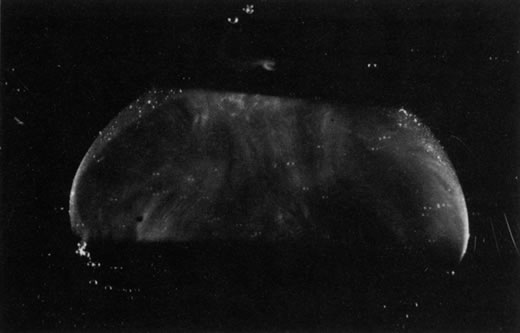

Vitreous cysts are generally benign lesions that are found in eyes with abnormal regression of the anterior18 or posterior19 hyaloid vascular system; otherwise normal eyes20,21; and eyes with coexisting ocular disease, such as retinitis pigmentosa22 and uveitis.23 Some vitreous cysts contain remnants of the hyaloid vascular system,24 supporting the concept that the cysts result from abnormal regression of these embryonic vessels.25 However, one histologic analysis of aspirated material from a vitreous cyst purportedly revealed cells from the retinal pigment epithelium.26 Vitreous cysts are generally not symptomatic and thus do not require surgical intervention. However, argon laser photocoagulation has been employed, and a recent report27 described the use of neodymium:yttrium-aluminum-garnet (Nd:YAG) laser therapy to rupture a free-floating posterior vitreous cyst.